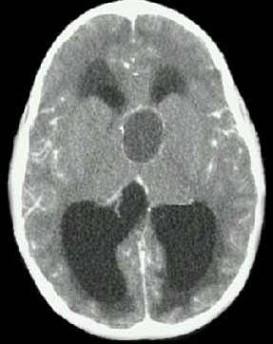

问题 女,38岁,闭经、嗜睡、尿多、视物模糊半年,精神烦躁,CT、MRI检查如图,最可能的诊断为()

选项 A.颅咽管瘤 B.脑膜瘤 C.蛛网膜囊肿 D.垂体瘤 E.表皮样囊肿

答案 A